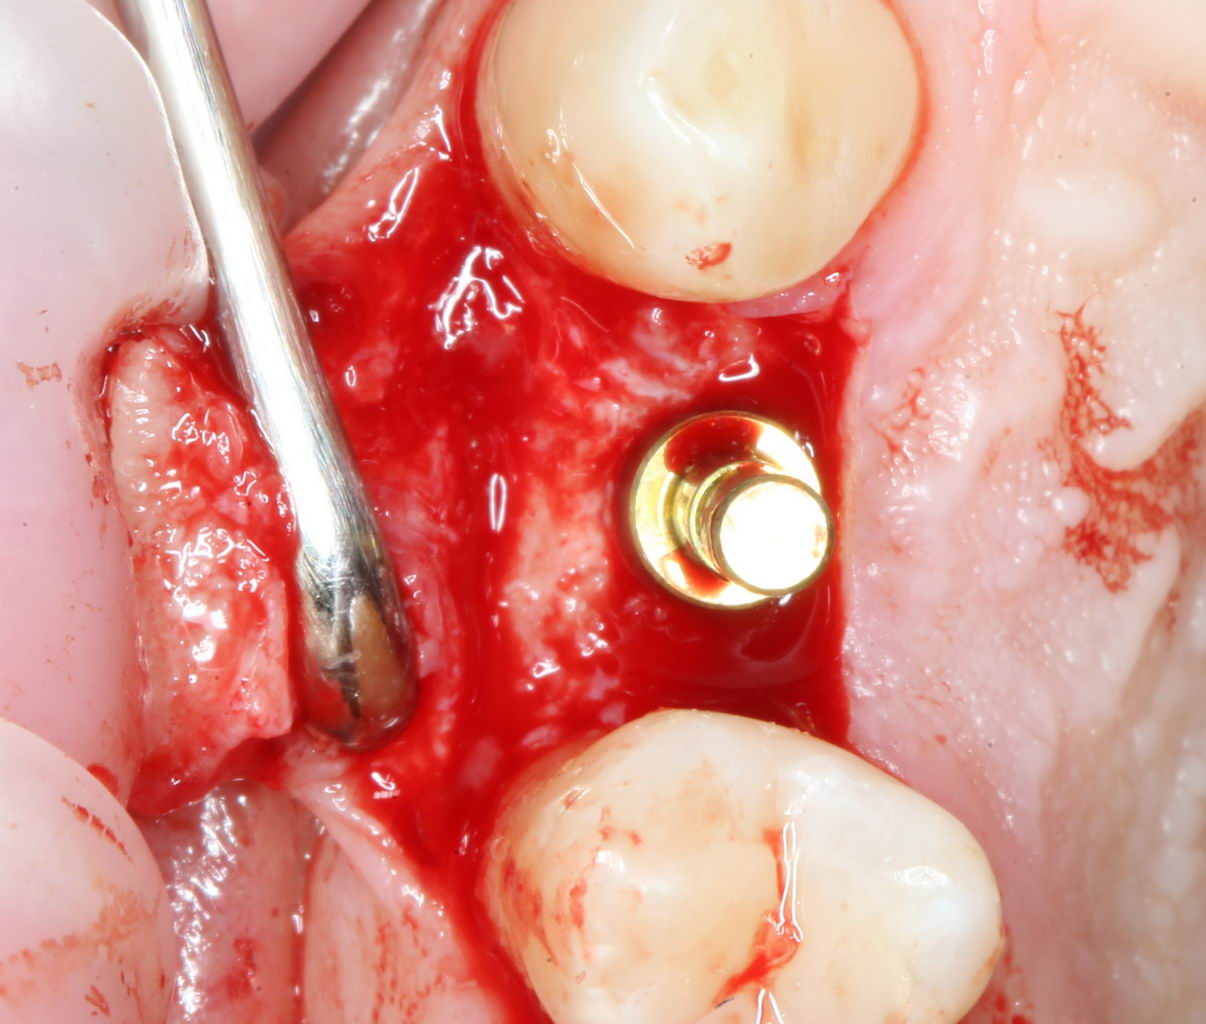

Затем рана скелетируется, открывается кость верхней челюсти:

Поскольку ранее мы сделали и внимательно изучили компьютерную томографию, то для нас никаких неожиданностей на этом этапе нет и быть не может. Мы спокойно приступаем к подготовке лунки под имплантат.

Подготовка лунки под имплантат (препарирование).